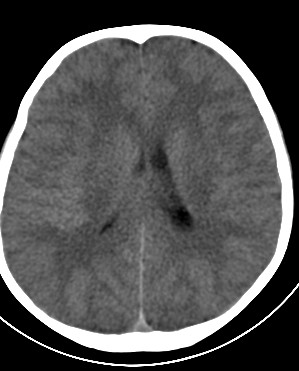

外伤一天,m,21y,骨窗示右颞骨骨折.

请大家看看,是脑内还是脑外(硬膜下还是硬膜外).请说说理由.谢谢.

脑内及脑外并存。即:脑挫裂伤并硬膜下血肿。原因:1 后方条片状高密度影周围见水肿带。2 同侧上方 硬膜下间隙增宽。

脑内脑外全有,上方比较局限近似梭形改变,考虑硬膜外血肿。没有跨过颅缝,且是脑膜中动脉所在的位置。中线移位,占位效应明显。后方条带状增高影,周围有水肿带,考虑脑内血肿。

右颞叶见混杂密度灶(以高密度灶为主)右侧脑室受压变形,中线结构左移,右颞部颅骨内板下见弧形高密度灶,右侧裂池及部分脑沟内见高密度灶;

结论:1:右颞叶脑挫裂伤;

2:右侧硬膜下血肿;

3:蛛网膜下腔出血。